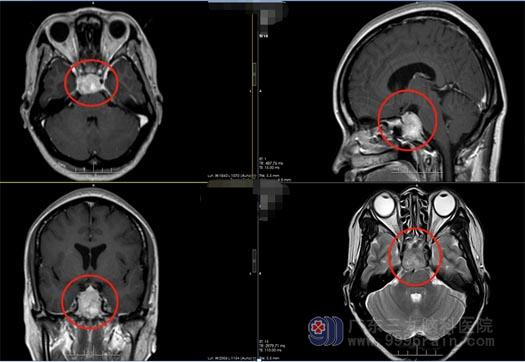

黄阿姨1个月前出现右侧眼球不能向外转动,在当地医院眼科就诊,对症处理后未见明显改善。之后,头颅MRI检查发现:斜坡占位。

广东三九脑科医院副院长鲁明接诊后,经过仔细阅片,结合黄阿姨的临床症状,考虑脑膜瘤的可能较大,需要手术治疗。